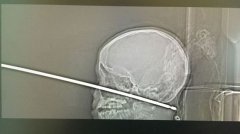

- 命大! 美国10岁男孩头部险些被金属烤肉杆刺穿

- 【环球网综合报道】据美国福克斯新闻网9月12日报道,美国密苏里州一10岁男孩爬树时意外跌下,一根约3.7米长的金属制烤肉杆径直刺入其头...